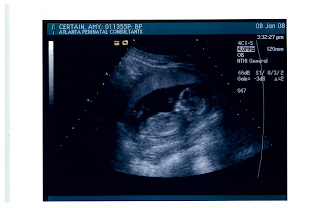

We went to the new Westside's Six Feet Under - SO fun and what a cool restaurant. Happy Birthday to my youngest sister, who isn't so young anymore. We missed you Jess & Garrison, Ryan, Matt & Joey. Happy Birthday Sissy, we love you!! Oh, and the general consensus is that I am definitely looking prego! Yay, Baby on Board!